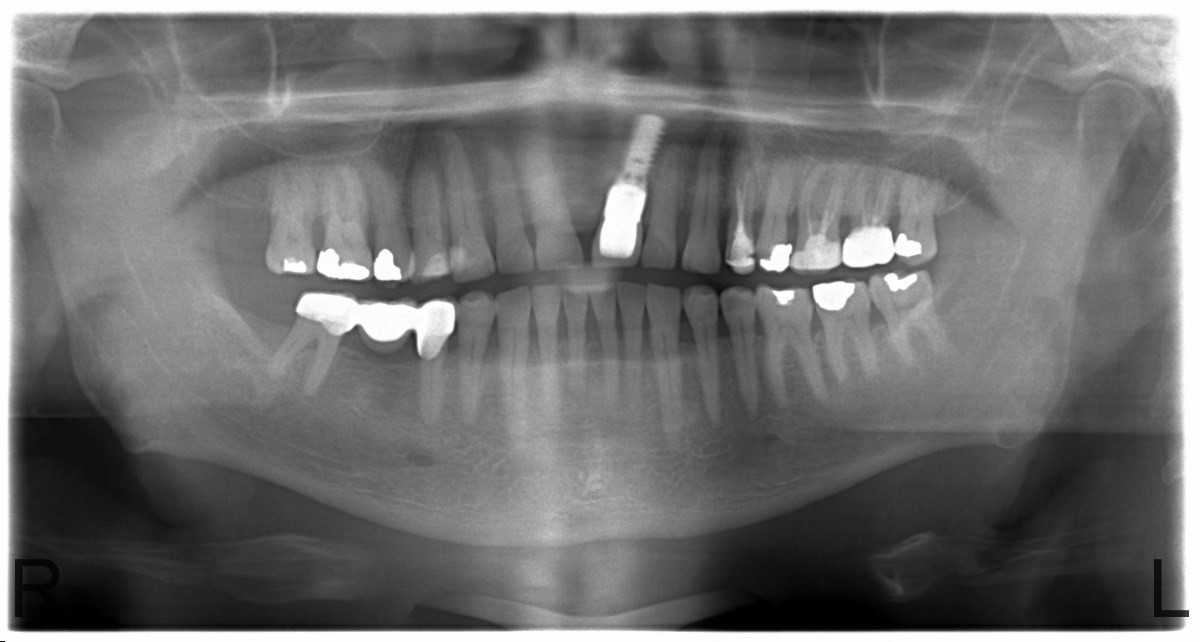

Implantát v postranním úseku chrupu.